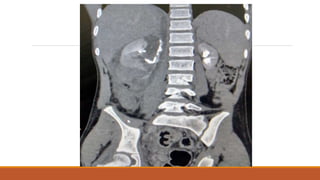

14 year old boy, presented to ER department with history of RTA on 16/2/23 ( hit by bike while

crossing the road), his abdomen was distended and tender, he was having vomiting and

hematuria, after resuscitation USG done which showed sub-capsular hematoma of about 150-200

ml, Renal Tri-phasic CT scan showed.

Case Scenario 14 yearold boy, presented to ER department with history of RTA on 16/2/23 ( hit by bike while crossing the road), his abdomen was distended and tender, he was having vomiting and hematuria, after resuscitation USG done which showed sub-capsular hematoma of about 150-200 ml, Renal Tri-phasic CT scan showed.